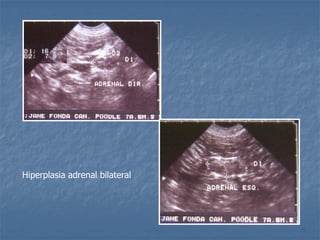

Hiperplasia adrenal bilateral

 Hiperadrenocorticismo  Hipofisáriodependente: há um aumento bilateral (80% dos casos!), pode ser simétrico ou assimétrico * Medida normal de espessura menor que 0,74cm cães adultos